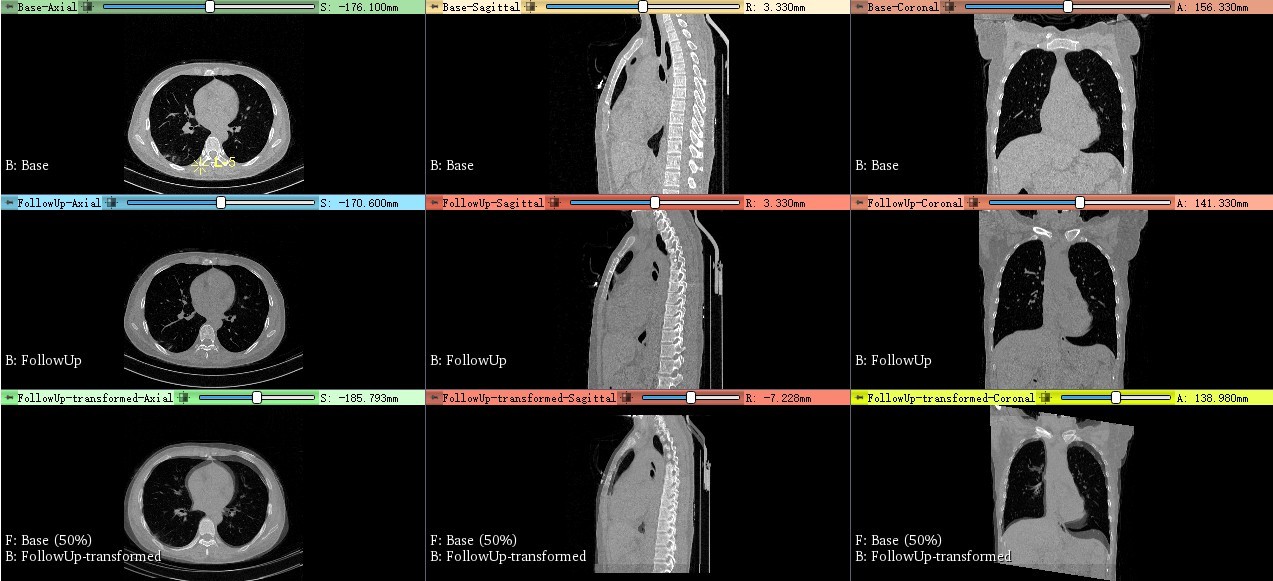

指定好固定和浮动图像之后,3D Slicer会非常贴心的自动把图像显示布局切换为3x3布局,如下图所示。

注意观察每个图像窗口的左下角,可以看出来,第一行显示的是固定图像3个正交切面;第二行是浮动图像3个正交切面;第三行则是固定和浮动图像以半透明方式叠加显示。从第三行可以看出,在固定和浮动图像的初始配准位置上,脊椎存在比较明显的偏差,也就是没对齐。

道理扯了一堆,实际效果到底如何。来看图片。先看下面的未配准之前的对比图片。这里的对比就是采用的前面说的Flicker显示方式。

再看配准之后的对比图片。大家注意,咱们只关心脊椎的配准,其他区域不关心啊。这个是“局部配准”的中心思想。

选择最能体现脊椎整体的矢状面,在两个不同层面截图,单独看一下。

至于标志点的具体添加位置,和具体病例密切相关,所以这里不具体介绍了。总体上,上面的数据添加了10对标志点,而选择Affine Registration还是ThinPlate Registrationd对配准效果影响不大。需要这么多对标志点的主要原因,是因为脊椎在前后两次扫描中,弯曲程度不同。